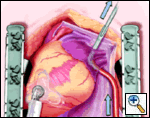

The pericardial sutures are withdrawn and the right hemisternum elevated by placing a folded towel under the lower right side of the sternal retractor, and an apical suction device (Urchin or Starfish [shown at left] Medtronic) attached to the cardiac apex. The heart is gently positioned similar to a ramus or high marginal coronary artery exposure. The left atrial appendage (LAA), and left sided pulmonary system should be in relatively clear view (LPA, LSPV, and LIPV).